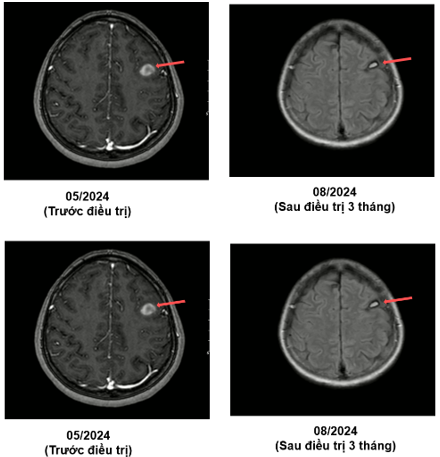

MRI sọ não (05/2024):

Hình 1: Hình ảnh các khối, nốt tổn thương có chảy máu thùy trán phải, góc cầu tiểu não trái, các nốt chảy máu thùy trán trái, thùy thái dương - thùy chẩm phải - theo dõi các tổn thương thứ phát.

MRI sọ não sau điều trị:

Theo dõi định kỳ bằng lâm sàng, chụp CT ngực và MRI sọ não sau 3 tháng, 6 tháng và 15 tháng cho thấy:

- Tổn thương phổi và não giảm kích thước rõ rệt.

- Không xuất hiện tổn thương di căn mới.

- Tình trạng toàn thân ổn định, chất lượng sống được cải thiện.